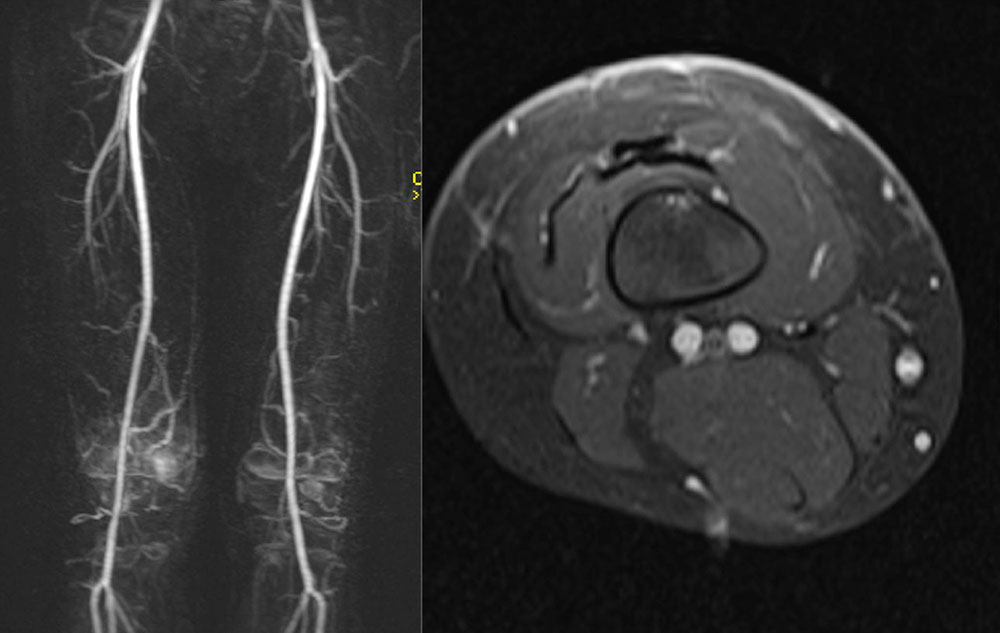

Positive reports of the use of sirolimus in individual case studies and smaller series of patients with extensive vascular malformations and corresponding severe clinical presentations have been published since 2011.

Sirolimus seems to be especially effective in the case of extensive, severe micro- or macrocystic lymphatic malformations.

There are also positive reports of the treatment of intraosseous lymphatic malformation in Gorham-Stout disease or generalized lymphatic anomaly. In the meantime, several publications report the use of sirolimus in kaposiform hemangioendothelioma with positive results so far. An international prospective multicenter phase II and phase III study has been initiated.

There are also publications on the use of sirolimus to reduce gastrointestinal bleeding in venous malformation of the intestinal mucosa, especially in blue rubber bleb nevus syndrome. Reductions of the volume of the lesions have also been reported in this situation.

A questionable effect or no effect in reducing bleeding frequency and proliferation activity in severe, complicated arteriovenous malformations has also been reported. The treatment outcome in fast-flow malformations appears to be significantly smaller and could not be demonstrated in all studies. The reason for this may lie in the genetic basis of arteriovenous malformations where dysregulation of another signaling pathway (RAS/MAPK/ERK signaling cascade) seems to be affected. By contrast, in slow-flow malformations upregulation of the PIK3CA/AKT signaling pathway is causative in the development of vascular anomalies. Sirolimus (rapamycin) is a central inhibitor of this mammalian target of rapamycin (mTOR) pathway, which may explain its effect.